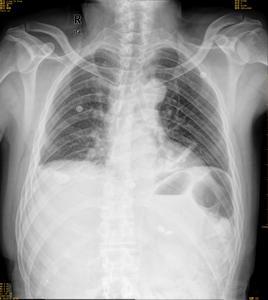

肺栓塞可由普通X线平片、血管造影、CT和MR以及核素扫描等方法检查。

肺动脉小分支的单发肺栓塞X线可无异常表现,大分支及多发性小分支栓塞X线可见X线异常表现。

(1)肺缺血:当肺叶或肺段动脉栓塞时,相应范围的肺纹理减少或消失,透亮度增加,称为韦斯特马克(westmark)征。多发性小动脉栓塞引起广泛性肺缺血。

(2)肺动脉异常:病变的肺动脉因血栓嵌塞而增粗,其远端因血流减少而变细。SCT显示明确.

(3)肺体积减小:下叶肺栓塞多见,故肺体积缩小也于下叶常见,引起膈升高,肺门及叶间裂下移。并可合并盘状肺不张。

(4)心影增大:心影增大由右室增大所致,见于较大肺动脉的栓塞或多发肺栓塞.

X线,SCT和MRI可以得以明确.

由于肺梗塞大都发生在患有心肺疾患的病人中,所以如在胸片上同时见有肺心病、肺淤血以及肺水肿等征象时,则应考虑肺部实变为肺梗塞的可能。在无心肺疾病的病人中,肺梗塞可引起肺出血而不产生肺梗塞,此时肺出血的X线表现不易与肺梗塞区别。当心肺无其他明显改变可提示肺出血可能性大。单纯肺出血可于7-10天或更短时间内完全消失,并无残留痕迹,肺梗塞的消退较为缓慢,平均需要20天左右,可长达5周,大多数病例可残留纤维瘢痕的索条状阴影。